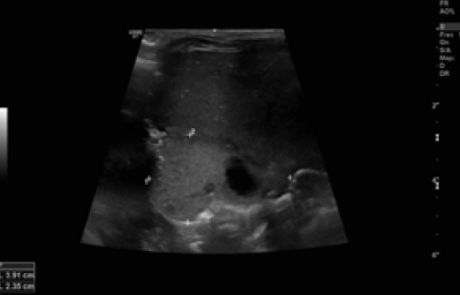

Durante su estancia en la Unidad se realizó una radiografía de tórax al ingreso (figura 1) y controles ecográficos seriados (figuras 2 y 3) en los que se objetivó la lesión quística en la base del pulmón derecho. Se mantuvo una actitud expectante dada la estabilidad clínica del paciente.